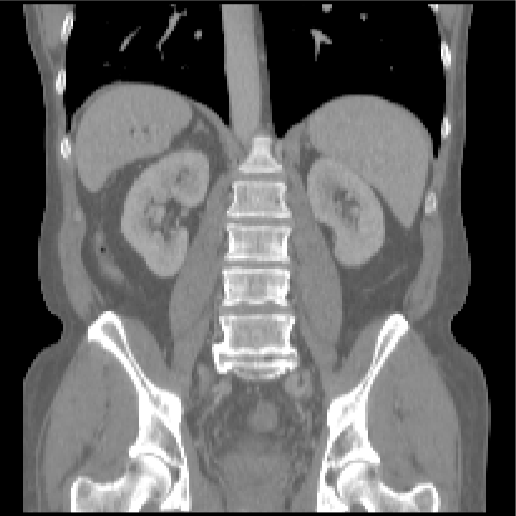

Abdomen CT-CT

This task tackles inter-patient registration of abdominal CT scans, which enables statistical modelling of variations of organs for abnormality detection, and can provide a canonical atlas space for further investigations. The dataset contains 50 abdominal CT scans (30/20 for training/testing) with 13 manually labelled anatomical structures: spleen, right/left kidney, gall bladder, esophagus, liver, stomach, aorta, inferior vena cava, portal and splenic vein, pancreas and left/right adrenal gland. Data acquisition and annotation protocols are detailed in [12]. The images were registered affinely in a groupwise manner and resampled to the same voxel resolution and spatial dimensions (192×160×256192160256192{\times}160{\times}256).